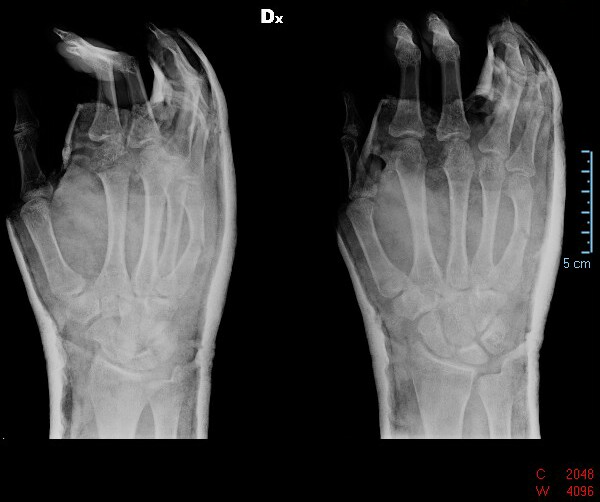

Salve sono un ragazzo di 17 anni che ha subito una forte contusione provocando una frattura composta del V metacarpo della mano dx. Recandomi in pronto soccorso mi hanno fatto un rx e ingessato bloccando mignolo e anulare per 30 giorni.. siccome sono già 8 giorni che porto il gesso ( premetto che mi sono recato in ps dopo 7 giorni, pensando fosse una contusione) la mia domanda è, guardando il tipo di frattura, siccome non sopporto il gesso per il caldo è per i fastidi che provoca.... Posso già toglierlo? La frattura di consoliderà lo stesso? Cosa potrebbe succedere?

Commento file: Rx dopo 7 giorni